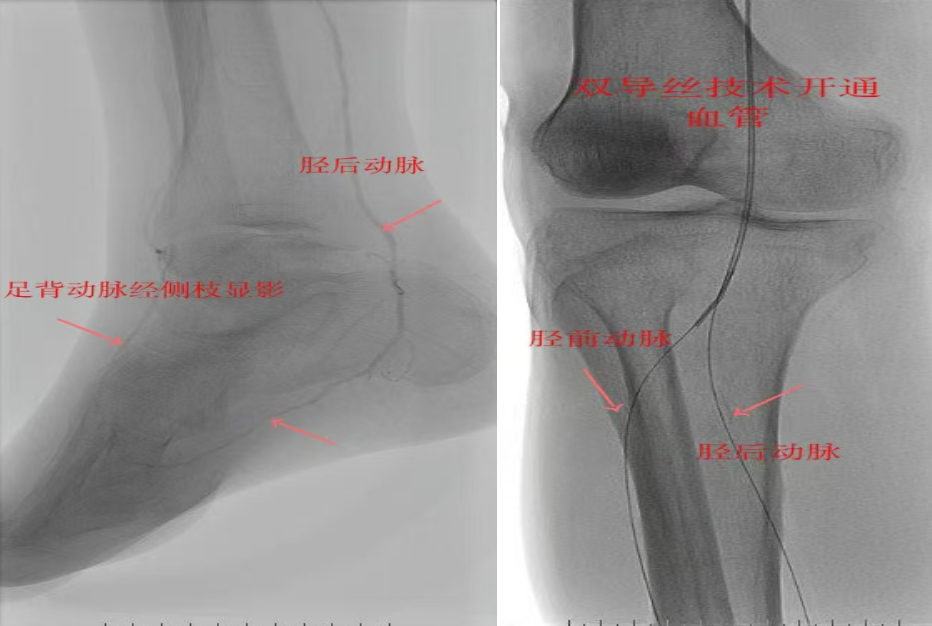

67岁女性患者,多年糖尿病、冠心病史,因右足溃烂伴凉麻疼痛长达2年就诊,此前曾接受外院介入术后血管再度闭塞。此次检查发现其股浅动脉、腘动脉至膝下血管全程闭塞,且伴有严重钙化。团队迎难而上,创新性经足背动脉逆向穿刺,耗时3小时成功贯通胫前动脉。术后当夜患者足部即感回暖,溃烂足趾疼痛显著缓解。术后结合中药外治(换药、熏洗、去腐生肌膏外敷)加速创面愈合。该患者已于出院,院外换药治疗。

影像检查:股浅动脉、腘动脉至膝下血管全程闭塞伴严重钙化。